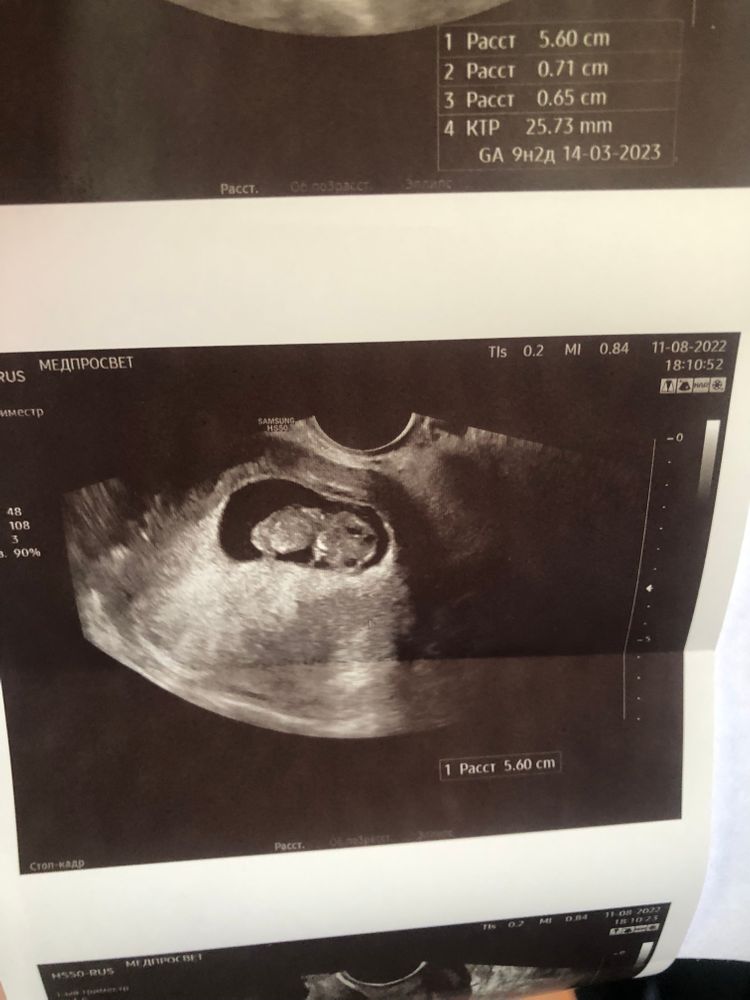

Стал сегодня живот немного болеть, даже можно сказать тянуть и покалывать то там, то тут. Мне врач говорила, если что-то беспокоит, звони, приходи, любой врач примет (мой врач в отпуске сама до 12 числа, но предупредила меня до отпуска, что делать в случае чего). Я звоню в ЖК, хочу записаться или просто подойти к доктору к любому (хотела узнать в какое время мне можно подойти, чтобы туда не переться впустую), чтобы посмотрели, сделали узи, ну или сказали чем снять спазм. Берет трубку админ в регистратуре, и я ей объясняю ситуацию: «Тянет живот, 10ая неделя беременности, можно мне сегодня попасть к врачу?», на что она мне отвечает: «Вызывайте скорую». Я мягко говоря в шоке, человек без мед.образования вместо того, чтобы записать, предложить когда подойти и т.д. мне говорит что делать. Или просто ответственность с себя снимают в ЖК, чтобы лишний раз не париться. Конечно же я позвонила в мед.центр и записалась к платному врачу, к которому ходила на 5ой неделе. Приехала, сделал узи, с малышом все хорошо, растет как положено, ктр 26мм. Со мной тоже все хорошо, увидел гематому 7 мм🤷🏻♀️ поэтому и тянет живот. Нахожусь на больничном, никуда не хожу, много лежу, не скачу, на работу не езжу, откуда взялась непонятно.

Ну и немножко фоточек малыша прикреплю😍 Сердечко дали послушать, так громко и часто бьется😍 (ЧСС 189 уд/минуту)